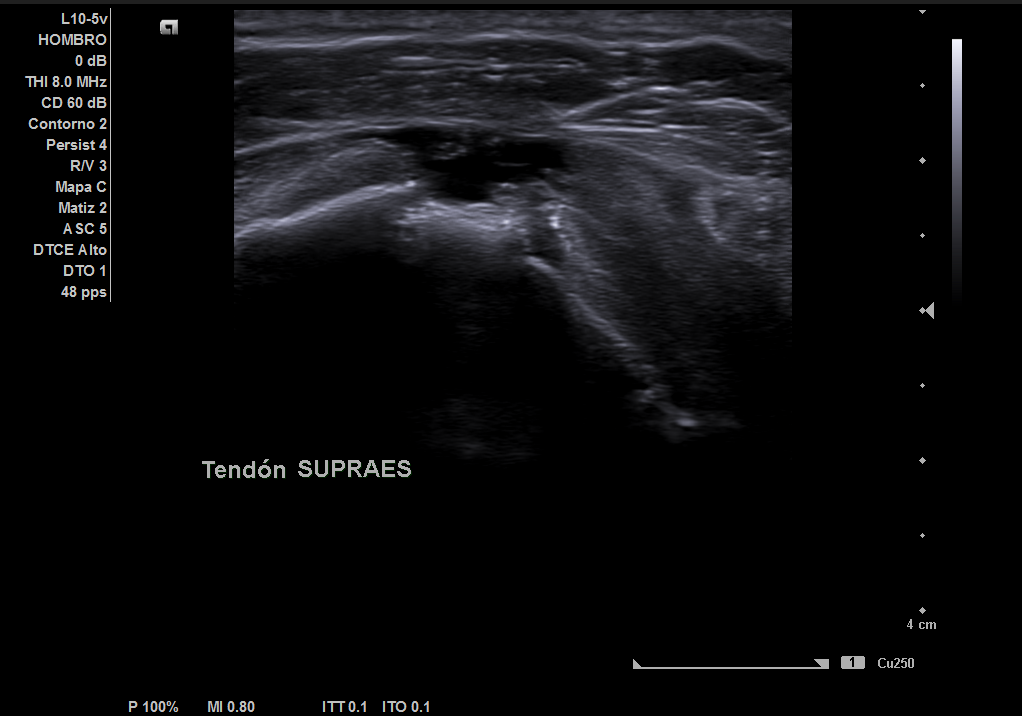

Descripción de los hallazgos ecográficos y las imágenes más relevantes para la resolución del caso

En la ecografía realizada observamos una rotura completa del tendón supraespino, rotura parcial del subescapular y severo derrame peritendón del bíceps junto con derrame articular glenohumeral.

Juicio diagnóstico: rotura manguito de los rotadores (rotura completa supraespinoso).